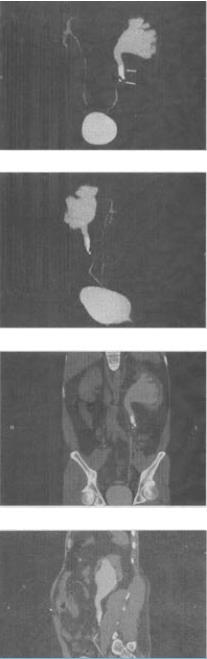

- 单项选择题 男,42岁,反复左侧腰部疼痛伴血尿3个月余,CT检查如图,下列说法错误的是()。

A、左侧输尿管内可见多发的高密度影

B、左侧输尿管上段扩张

C、左侧肾盂肾盏扩张

D、左输尿管结核并左肾积水

E、考虑为左输尿管结石并积水